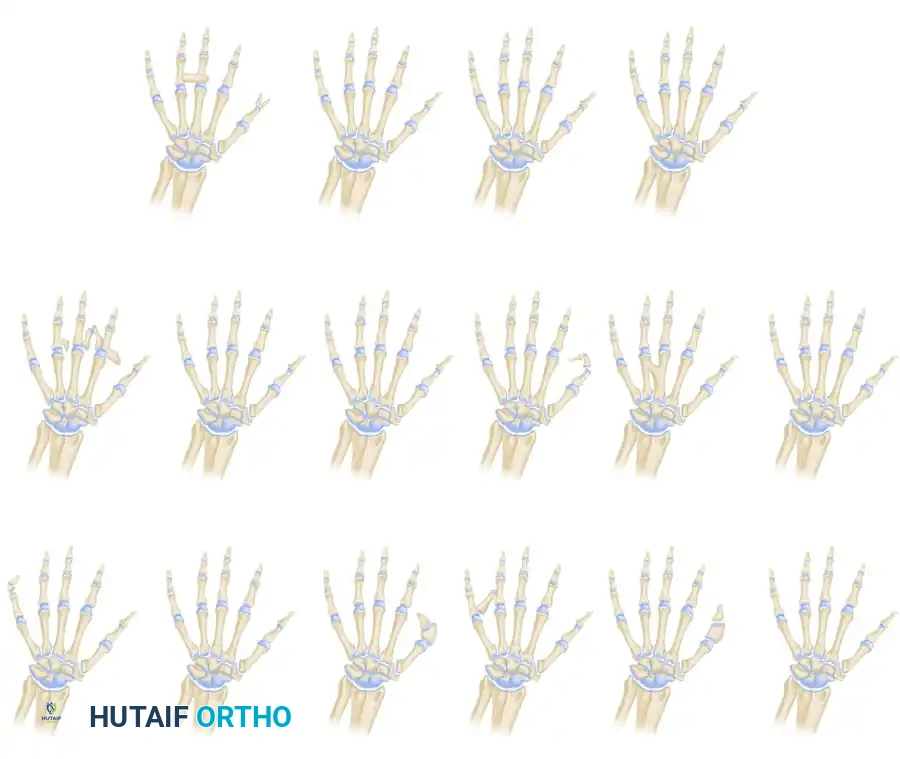

Classification Systems

Understanding the morphological pattern is critical for surgical planning. The deformity is broadly categorized into typical and atypical patterns.

1. The Typical Pattern (True Cleft Hand)

Present at birth, this pattern features a central V-shaped defect in the palm. The long finger is usually entirely absent. The remaining digits bordering the cleft (index and ring fingers) frequently exhibit varying degrees of syndactyly and a deficient, narrowed first web space. The deformity is often bilateral and inherited in an autosomal dominant pattern with variable penetrance. Foot deformities (cleft foot) are frequently associated.

2. The Atypical Pattern (Symbrachydactyly Variant)

In the atypical pattern, the hand typically presents with only two digits: one on the radial border (thumb) and one on the ulnar border (small finger). A shallow U-shaped defect intervenes along the distal palm. The deformity is usually unilateral, sporadic, and lacks associated foot anomalies. In severe forms, all digits except the small finger may be absent.

Flatt’s classification of central deficiencies: Group 0, all bones present; Group 1, one ray involved; Group 2, two rays involved; and Group 3, three rays involved.

Radiographic Evaluation

Radiographs are essential to identify transverse bones, delta phalanges, and carpal coalitions (which become apparent in older children). Goldfarb et al. introduced the measurement of metacarpal and phalangeal divergence angles to assist in preoperative planning and to objectively assess postoperative reconstruction success.